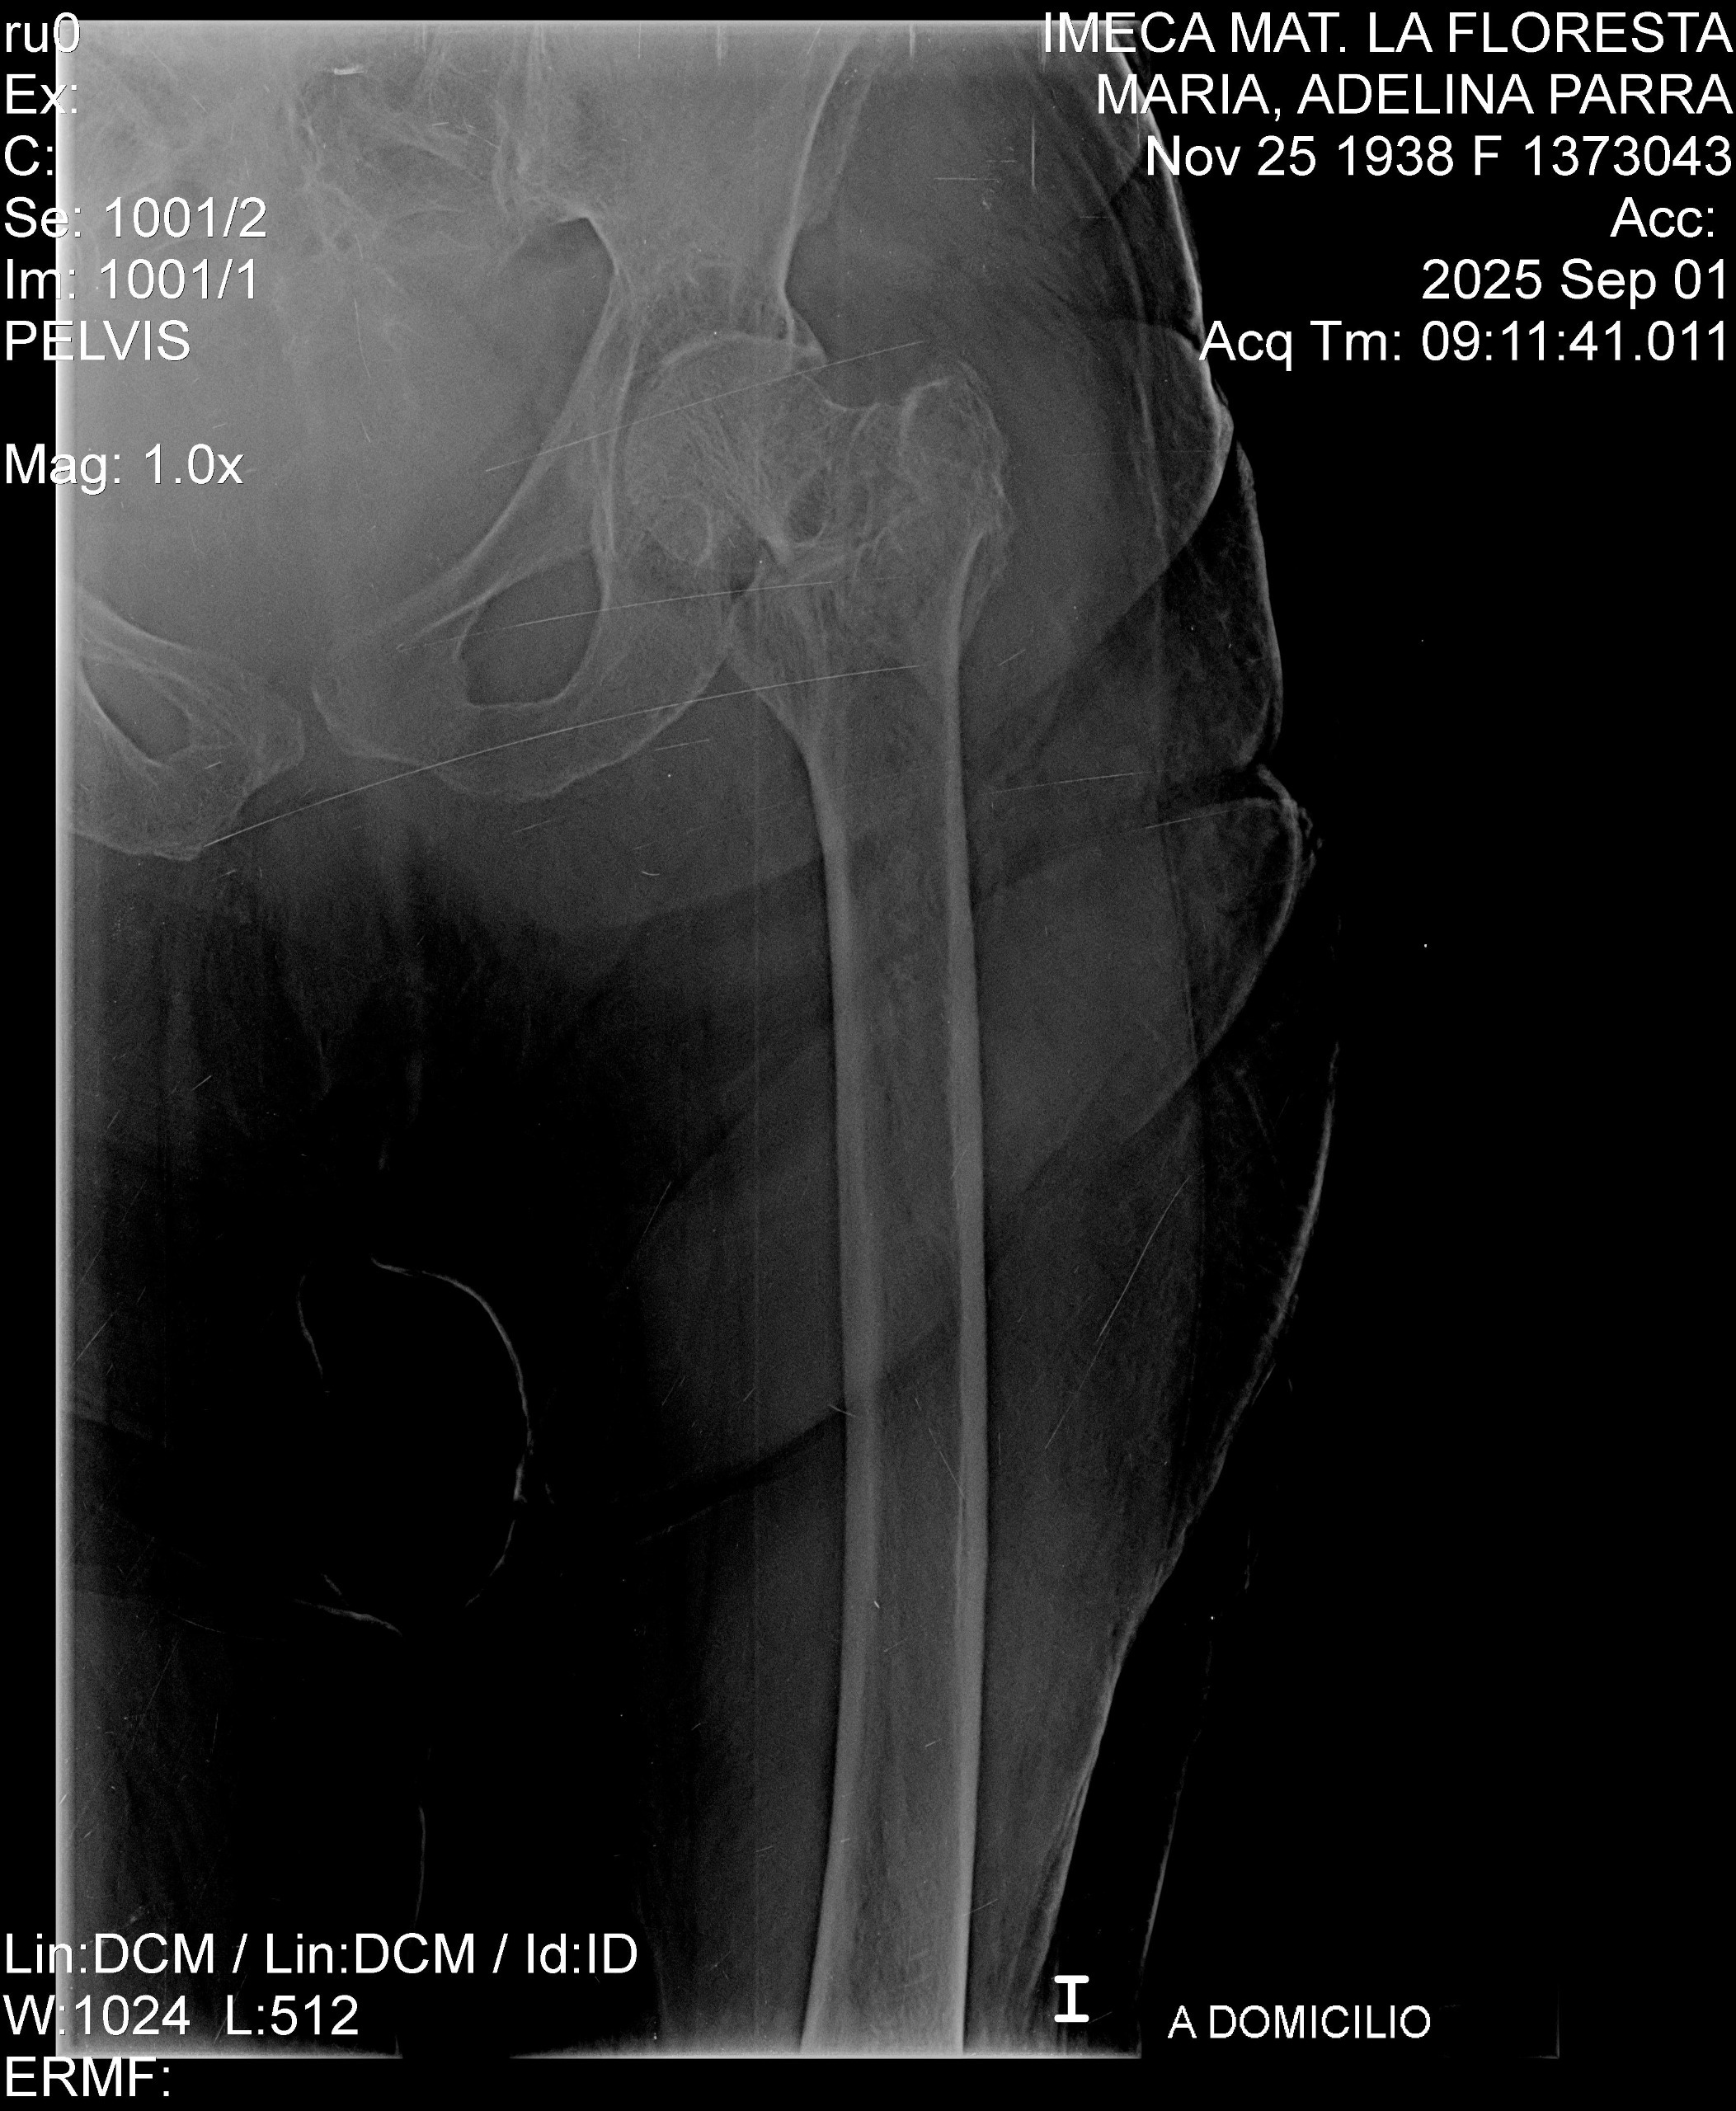

Recently, my grandmother suffered a terrible fall and fractured her left femur. She now requires extensive surgery to replace the femur, and the medical expenses are overwhelming. Our family is doing everything we can to support her, but the costs of the surgery, hospital care, and recovery are far more than we can manage alone.

Recientemente, mi abuela sufrió una fuerte caída y se fracturó el fémur izquierdo. Ahora necesita una cirugía extensa para reemplazar el hueso, y los gastos médicos son abrumadores. Aunque nuestra familia está haciendo todo lo posible para apoyarla, los costos de la cirugía, la atención hospitalaria y la recuperación superan lo que podemos manejar solos.